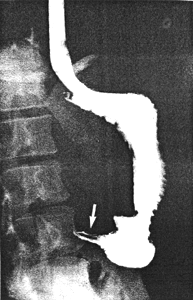

Case 26.3. E.W., female aged 34 years. Having swallowed 4 mouthfuls of barium in the erect position, the patient suddenly started to retch; barium had reached the pyloric aperture but had not traversed it, while some was still in the oesophagus. As soon as retching started a film was exposed. This showed contraction of the left pyloric loop with a "round" collection of barium on its aboral side, i.e. in the sphincteric cylinder (Fig. 26.3A). A segmental or systolic contraction of this collection followed, terminating in a tightly contracted cylinder containing a longitudinal mucosal fold (Fig. 26.3B); this corresponded to maximal contraction of the sphincteric cylinder. During contraction barium contained in the cylinder was propagated not into the duodenum, but in a retrograde way into the more proximal part of the stomach. When retching ceased, normal cyclical contractions of the pyloric sphincteric cylinder and gastric emptying commenced. No organic lesion was found.

| Fig. 26.3. A Case E.W. Contraction of left pyloric loop (curved arrow). Round collection of barium in partially contracted sphincteric cylinder (straight arrow). B Case E.W. Maximally contracted sphincteric cylinder containing a longitudinal mucosal fold (arrow). | |